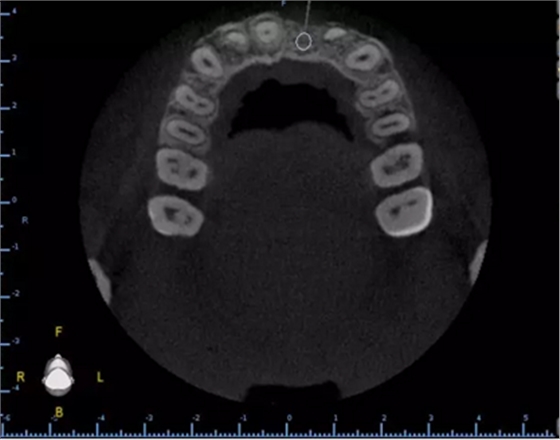

2.術(shù)前植體設(shè)計(jì)

3.術(shù)前導(dǎo)板設(shè)計(jì)